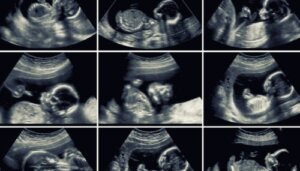

In het algemeen is deze echografie 2D. Als het apparaat het echter toelaat, kunnen sommige beelden in 3D of 4D worden vastgelegd. Dit laatste toont de gelaatstrekken van de baby met grotere precisie en toont zelfs de bewegingen in real-time.

De specialist kan 2D en 3D beelden combineren voor een meer complete analyse van alle structuren van de baby.